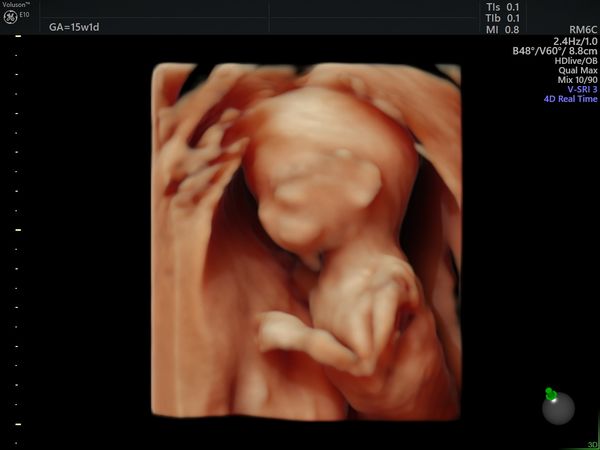

После скрининга пациентка пришла на УЗИ в 15 недель и 1 день. По УЗИ определялся один плод мужского пола, размеры плода пропорциональные, соответствовали менструальному сроку. Вес — 121 г (52 процентиль — норма). Пороков развития на момент исследования не было выявлено.